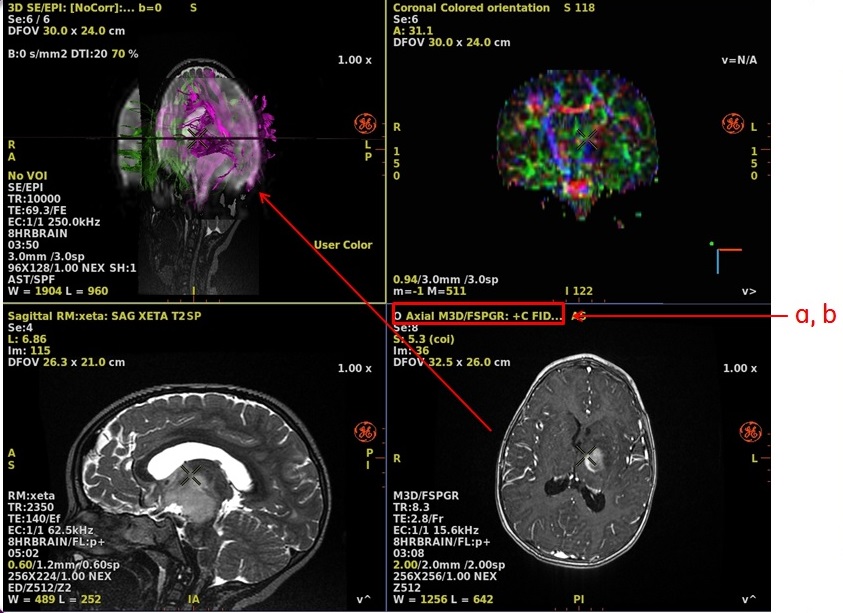

- To merge the 3D views with the FiberTraks, follow these steps.

- From the sagittal color orientation viewport, click on Color orientation and select the 3D view.

Figure 5. Color orientation

- From the plane selection menu, click Sagittal.

- Scroll through the images to locate an image that displays the pathology of interest.

- With the mouse in

, click an image and drag it over the FiberTrak viewport and drop it in the "Drop here to merge the views" box.- Respond to any prompts

- From the coronal orientation viewport, click Color orientation and select the 3D view.

- From the plane selection menu, click Coronal.

- Scroll through the images to locate an image that displays the pathology of interest

Figure 6. Merge views

- Respond to any prompts